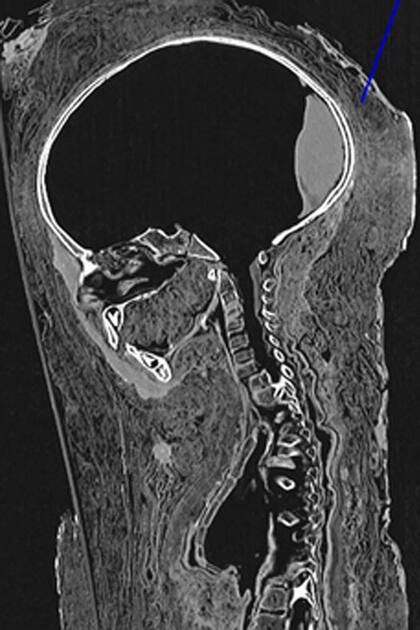

Un equipo de científicos logró reconstruir el rostro de un niño egipcio que fue momificado hace 2000 años basándose en un retrato y en una tomografía computada con imágenes 3D.

Según el estudio de los investigadores, los resultados de la tomografía mostraron que el retrato pintado del niño, que se hallaba colocado sobre la cabeza de la momia, se aproximaba bastante al rostro original, salvo que en el dibujo parecía bastante mayor que los tres o cuatro años que en realidad tenía el infante cuando fue momificado.

Los investigadores emplearon estándares de niños modernos de entre tres y ocho años de edad con el objetivo de reconstruir el grosor de su piel. El color y las ondulaciones del cabello se recrearon a partir de la pintura y su rostro se basó en la forma del cráneo y los dientes de acuerdo con las imágenes de la tomografía, explicaron los investigadores.

La tomografía reveló que el cerebro del niño y algunos de sus órganos abdominales habían sido removidos, lo que se considera una tradición corriente en las momificaciones del antiguo Egipto.

El tamaño de 78 centímetros de altura junto con el desarrollo de los huesos y los dientes reveló una edad de entre tres y cuatro años en el momento de la muerte.